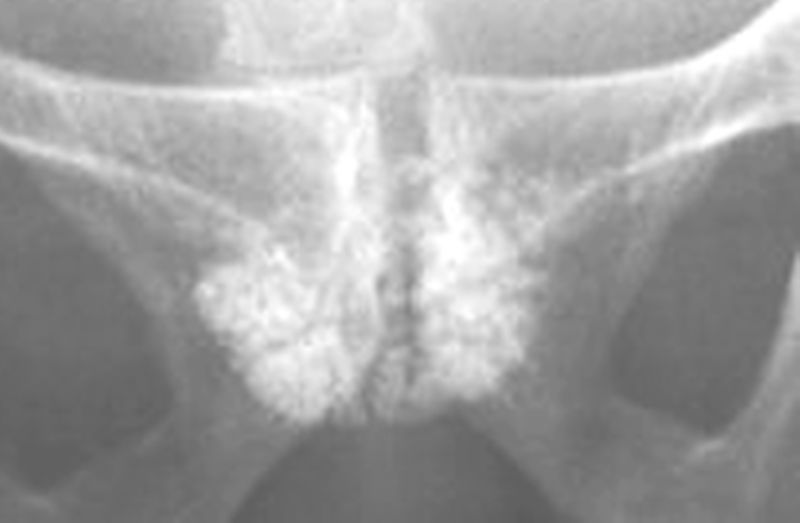

男性,55岁,请大家看看,这个片位于耻骨联合处是什么?

病史:排尿困难10年余,加重3天

迷漫性前列腺钙化

考虑:弥漫性前列腺点状钙化!

弥漫性前列腺点状钙化!